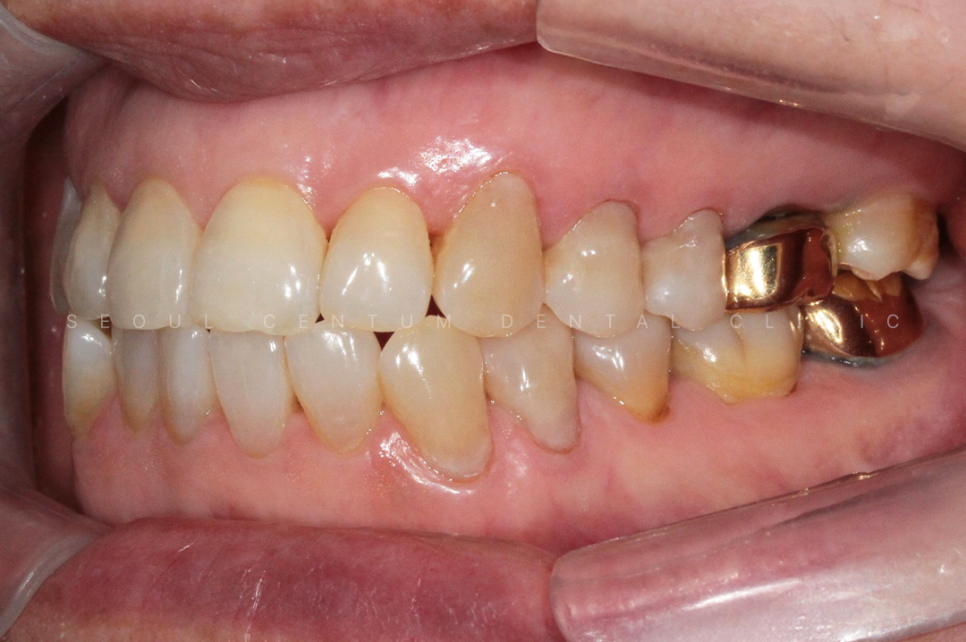

확실히 하고 안하고 심미적으로도

차이가 큰 편이기 때문에

하고나서 환자 본인도 만족도가 매우 높은

부분이라고 할 수 있겠습니다.

레진으로 깔끔하게 치료를 하니

심미적으로도 한결 보기 좋고

치아도 앞으로 보호가 되는 부분이라

안심하고 식사를 하실수가 있겠는데요.

이렇듯 하루에 문제가 해결되는

간단한 치료이며 외관적으로도

만족도가 굉장히 높은 부분입니다.